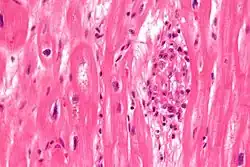

Microscopically, Aschoff bodies are areas of inflammation of the connective tissue of the heart, or focal interstitial inflammation. Fully developed Aschoff bodies are granulomatous structures consisting of fibrinoid change, lymphocytic infiltration, occasional plasma cells, and characteristically abnormal macrophages surrounding necrotic centres. Some of these macrophages may fuse to form multinucleated giant cells. Others may become Anitschkow cells or "caterpillar cells," so named because of the appearance of their chromatin.

They are pathognomic foci of fibrinoid necrosis found in many sites, most often the myocardium. Initially they are surrounded by lymphocytes, macrophages, and a few plasma cells, but they are slowly replaced by a fibrous scar. Aschoff bodies are found in all the three layers of the heart, least chance in the pericardium.

, occasional plasma cells, and activated macrophages (Anitschkow cells) pathognomonic of rheumatic fever. These macrophages have abundant cytoplasm and central round nuclei in which chromatin condenses into a central, slender, wavy ribbon, the reason why they are sometimes called "caterpillar cells". They are especially found in the vicinity of small blood vessels in the myocardium and endocardium and occasionally in the pericardium, and also the adventitia of the proximal part of the aorta. Lesions similar to the Aschoff nodules may also be found in extra-cardiac tissues.